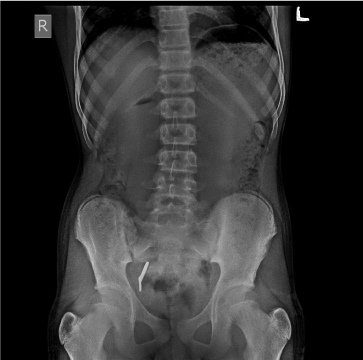

Another radiograph was taken after one and half hour. The mouth mirror head had crossed the narrowest ileo- caecal sphincter and had reached the large intestine (Figure 3). The patient was continued with the same diet. After 3 hours, during defecation, mouth mirror head was passed through his stools and confirmed with a radiopgraph (Figure 4)

Figure 3. Mouth mirror in ILEO CAECAL JUNCTION

Figure 4. No trace of instrument (after expulsion)